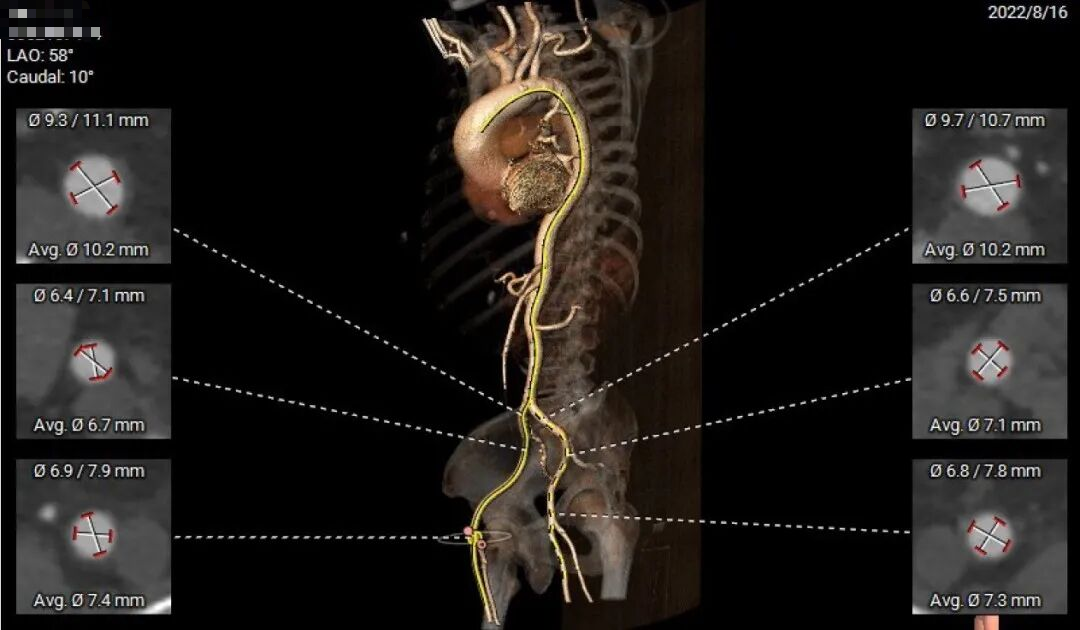

主动脉CTA评估:

患者为Type1带嵴二叶瓣,存在室间隔膜部瘤,左右融合嵴伴钙化,瓣叶增厚。

瓣环径26.2,LVOT 25.6,升主动动脉扩张,约44mm。

窦部空间可,双侧冠脉开口高度可。

横位心角度80°。

该患者存在起源于瓣环下的室间隔膜部瘤,该瘤体上缘延伸至瓣环上方7.2毫米(图B)。

为了更深入地理解此例二叶式主动脉瓣的解剖结构,评估解剖瓣环径线,在瓣环上方进行了多平面测量。

入路方面,主动脉弓大弯侧无明显钙化,双侧髂股动脉内径可,双侧股动脉分叉位于股骨头中下1/3。